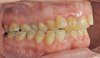

Das Quietschen fällt mir schon gar nicht mehr auf. Aber ich trage sie weiterhin fleißig. Ich kann schon sagen, dass sich der Zahn, gut eingestellt hat. Vor vier Monaten konnte ich noch die Kaufläche mit meiner Zunge beim zubeißen erfühlen. Das geht jetzt nicht mehr. Ich schaue mal, ob ich gleich noch die Fotos meiner KFO vor der Behandlung und von vier Wochen hochladen kann. Da kann man den Unterschied schon gut erkennen. Was ich als Laie halt so sagen kann. Außerdem habe ich das Gefühl, dass mein rechter vorderer Eckzahn etwas mehr Platz hat und nicht mehr so weit nach vorne steht.

Okklusion_rechts-Anfangsdiagnostik-2023_09_20-0_2[1].jpg Okklusion_Anterior-Anfangsdiagnostik-2023_09_20-0_1[2].jpg Okklusion_links-Anfangsdiagnostik-2023_09_20-0_3[1].jpg Okklusion_OK-Anfangsdiagnostik-2023_09_20-0_4[1].jpg Okklusion_UK-Anfangsdiagnostik-2023_09_20-0_5[1].jpg DSC_7646[1].JPG DSC_7649[1].JPG DSC_7651[1].JPG DSC_7652[1].JPG DSC_7655[1].JPG

Ich hoffe, ihr könnt auf diesen Bildern die Entwicklung sehen.